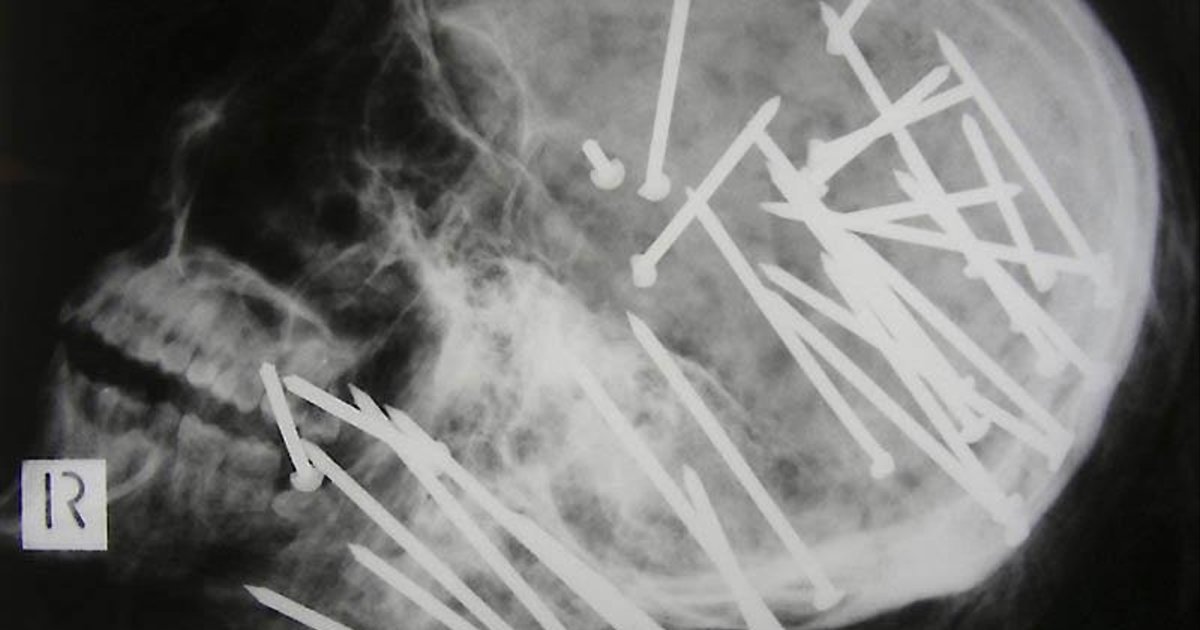

Гвоздь в человеческом черепе - пациент случайно выстрелил в себя из пневматического молотка. Он даже не понял, что выстрелил в себя - 10-метровый гвоздь обнаружили только через 6 дней.